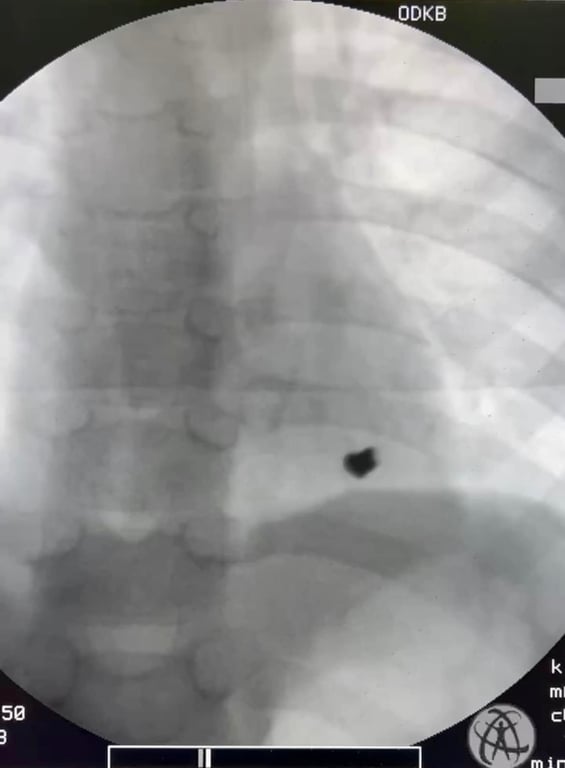

В Одеській дитячій обласній клінічній лікарні кардіохірурги провели операцію на серці дитини. 7-річний хлопчик отримав кульове поранення.

У суботу, 1 квітня, до медичного закладу була госпіталізована 7-річна дитина з травмою серця.

У лікарні зазначили, що гра двох братів 7-ми та 8-ми років гвинтівкою, яка була зарядженою, закінчилася пораненням лівої частини грудної стінки з проникненням кулі в порожнину перикарда (серцевої сумки) та ураженням задньої стінки лівого шлуночка серця.

"Дитина народилася у "сорочці", бо, на щастя, хлопчик був вчасно госпіталізований до Татарбунарської багатопрофільної  лікарні та переведений до нашого закладу,  де був прооперований в ургентному порядку нашими кардіохірургами — завідувачем відділенням серцево-судинної хірургії Володимиром Бузовським та лікарем серцево-судинним хірургом Олександром Гоцуляком. Вони виконали оперативне втручання на серці та врятували дитину", — розповів директор Одеської обласної дитячої клінічної лікарні Павло Георгієв.

Зараз дитина почуває себе краще. Хлопчик перебуває у післяопераційному періоді.